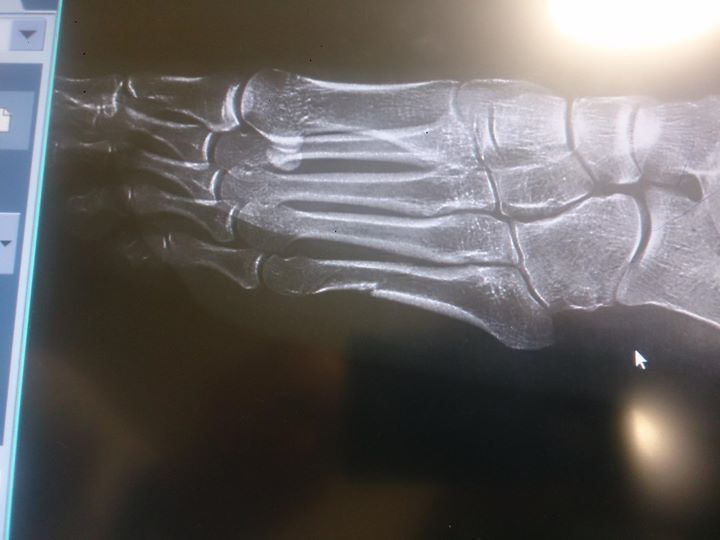

"Рентгеновский снимок моей ноги. Многоуровневый перелом. Привет всем "экспертам". Буду выступать дальше", – написала Ковальчик на своей странице в Facebook.

Юстина Ковальчик продолжит свои выступления на XXII Олимпийских зимних играх, несмотря на перелом стопы. Польская спортсменка повредила ногу еще до Олимпиады во время тренировок в Санта-Катерина. Эта травма не помешала ей начать выступления в Сочи и занять шестое место в скиатлоне.